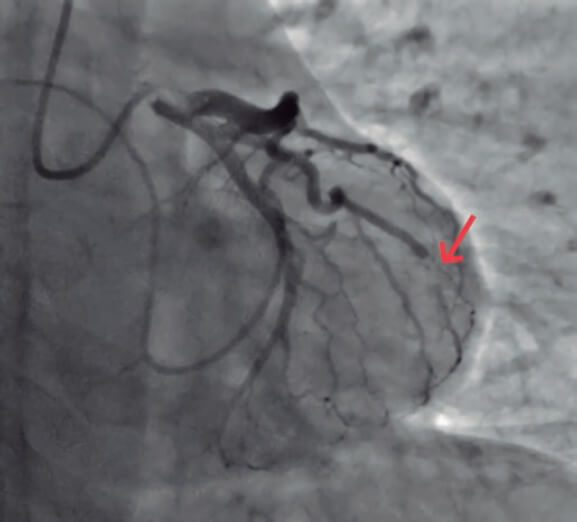

Se realizó una coronariografía precoz que mostró el trombo en la bifurcación distal de la arteria circunfleja (figura 1, flecha).

Figura 1.